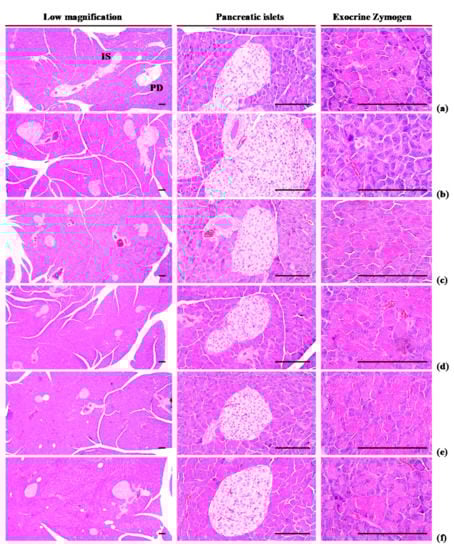

2.11. Histopathology

Following the organ weights being measured, 10% neutral buffered formalin was used to fix the left lateral lobe of the liver, splenic lobe of the pancreas, left periovarian fat pads, and abdominal wall deposited fat pads stuck to the muscularis quadratus lumborum. After paraffin embedding had been carried out embedding by automated tissue processor (Shandon Citadel 2000, Thermo Scientific, Waltham, MA, USA) and embedding center (Shandon Histocentre 3, Thermo Scientific, Waltham, MA, USA), a microtome (RM2255, Leica Biosystems, Nussloch, Germany) was used to make serial sections. Once the sections were ready, the hematoxylin and eosin (HE) staining were performed for light microscopy analysis (Eclipse 80i; Nikon, Tokyo, Japan). The histological observations of each organ were conducted using a light microscope equipped with a camera system (ProgResTM C5, Jenoptik Optical Systems GmbH, Jena, Germany) and an automated image analyze program (iSolution FL ver 9.1, IMT i-solution Inc., Vancouver, British Columbia, Canada). The operator was blinded to the group allocation during this analysis. Otherwise, dehydrated liver portions, with 30% sucrose solution, were divided using a cryostat and stained with Oil Red-O. To observe additional details regarding hepatic changes, mean hepatocyte diameters (under H&E staining) were determined in the restricted view fields. The regions of steatohepatitis regions (i.e., proportion of fat placed in regions of the hepatic parenchyma) were determined as the proportions of lipid placed regions between the limited histological sight field of the liver using Oil Red-O staining. Average diameters of hepatocytes were determined in the limited sight field on a monitor on paraffin-embedded sections stained with H&E by an automatic image analysis procedure as μm. In addition, the mean diameters of white adipocytes in each fat pad were calculated. The thicknesses of the deposited periovarian and abdominal wall fat pads (mm) was determined, along with average areas occupied by zymogen granules. The numbers of pancreatic islets were also measured diameters of the pancreatic islets. Blinded evaluation was carried out by the histopathologist.

3.1.5. Effects of WL on Exocrine Pancreas Zymogen Granule Content

Exocrine pancreas zymogen granule content was less (p < 0.01) in HFD control group than in intact control group, due to the discharge of zymogen granules. However, exocrine pancreas zymogen granule content significantly (p < 0.01) increased in three WL dosage groups and the metformin group, compared with the results in HFD control group. In particular, 50 mg/kg WL and metformin inhibited the HFD-induced exocrine pancreas zymogen granule depletions at histopathological levels (Table 4; Figure 5). The proportion regions of exocrine pancreas filled by zymogen granule in HFD control group were decreased −78.08% as compared to intact control group, but they were increased 210.39, 309.07, 259.93, and 217.69% in metformin 250 mg/kg, WL 200, 100, and 50 mg/kg groups as compared to those of HFD control group.

3.2.3. Effects of WL on Pancreatic Islet Hyperplasia and Expansion

Pancreatic islet mean diameters and numbers were significantly (p < 0.01) higher observed in HFD control group than intact control group because of marked pancreatic islet hyperplasia or component endocrine cells. Hyperplasia and expansion of islets decreased in a significant and dose-dependent manner (p < 0.01) in response to metformin treatment and each of the three WL dosages, compared with the results in HFD control group. In particular, 50 mg/kg WL and metformin inhibited the HFD-induced hyperplasia and expansion of pancreatic islets (Table 7; Figure 5). The mean pancreatic islet numbers in HFD control group were increased 344.74% as compared to those of intact control group, but they were changed by −48.52, −71.01, −62.72, and −49.11% in metformin 250 mg/kg, WL 200, 100, and 50 mg/kg groups as compared to HFD control group. The proportions of islet filled regions in HFD control group were increased 117.85% as compared to intact control group, but they were decreased −43.60, −53.28, −48.47, and −43.90% in metformin 250 mg/kg, WL 200, 100, and 50 mg/kg groups as compared to HFD control group.